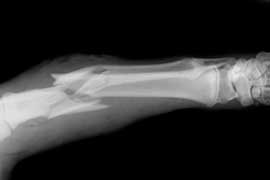

El efecto de la terapia con bisfosfonatos a largo plazo sobre la resistencia ósea trabecular y la densidad de microgrietas

18 diciembre 2017

Se halló reducción de la resistencia y un aumento de microgrietas en el hueso tratado con bifosfonatos. Bone Joint Res, 27 de octubre de 2017

El uso prolongado de bifosfonatos reduce la resistencia a las fracturas

03 agosto 2017

Luego de un uso promedio de 8 años, los bifosfonatos mostraban tejido cortical más mineralizado pero con menor resistencia al inicio y progresión de la fractura femoral. PNAS, 31 de julio de 2017